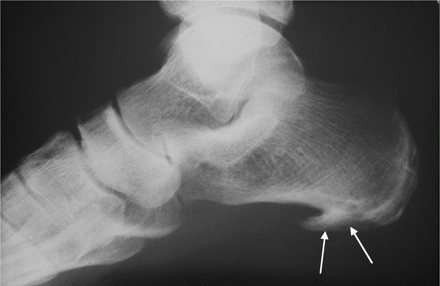

На рентгене новообразование выглядит как крючок или шпора, откуда и появилось название заболевания. Медицинский термин заболевания — плантарный фасцит.

- результаты рентгенографии (на поздних стадиях заболевания) и УЗИ.